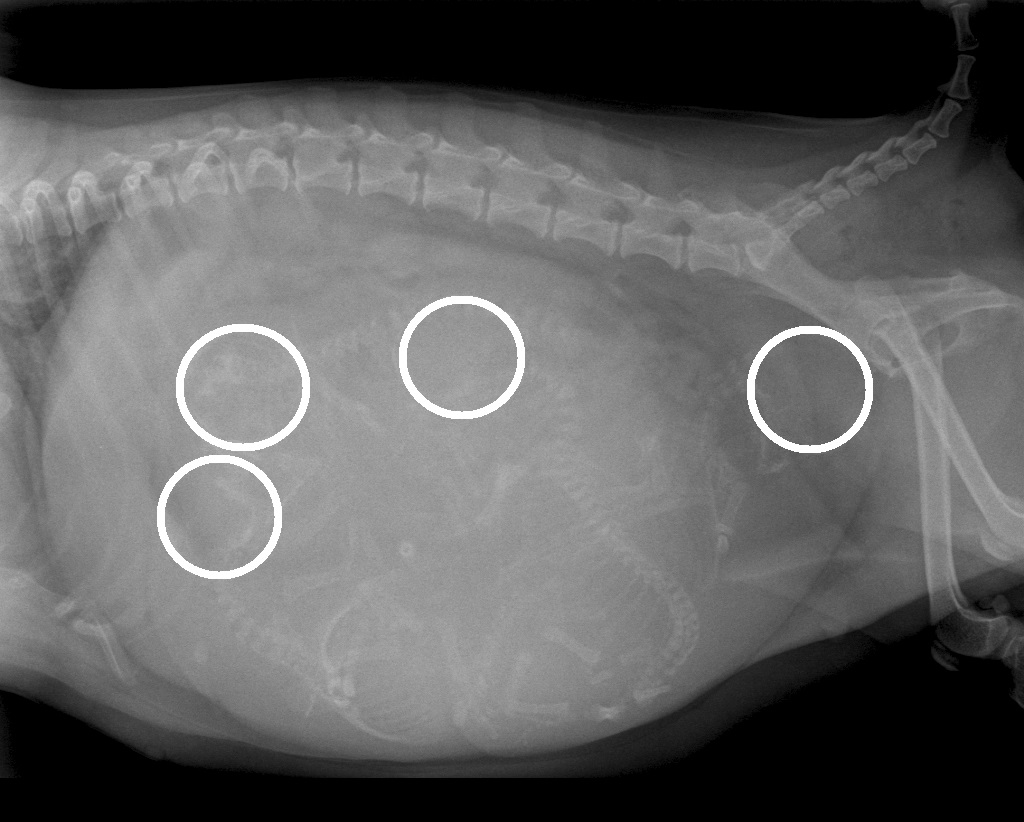

De bevalling stagneerde en het was voor ons zaak om snel te bepalen wat daar de oorzaak van was. Weeënzwakte? Of lag er een pup verkeerd? Of was de pup gewoon te groot voor het geboortekanaal? Omdat we weten dat chihuahua-pups nogal eens een te groot hoofdje hebben voor het bekken van de moeder besloten we direct een röntgenfoto van Luna's buik te maken. Op deze foto was goed te zien dat er inderdaad een pup met een fors koppie voor de bekkeningang vastliep en besloten we direct een keizersnede uit te voeren. Er werden vier mooie pups geboren, drie teefjes en een reu. Inmiddels zijn we anderhalve week verder en doen moeder en pups het fantastisch!

Röntgenfoto van Luna's buik: zoek de vier kopjes

De vier kopjes zijn wit omcirkeld

De meest rechtse ligt klem voor de bekkeningang van Luna